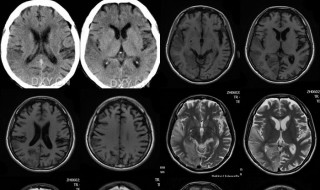

mr平扫是什么 是做什么的1、这是颈椎影像学诊断的名称。就是颈椎核磁共振检查,通常对颈椎部位的骨质以及软组织的疾病发现有帮助。